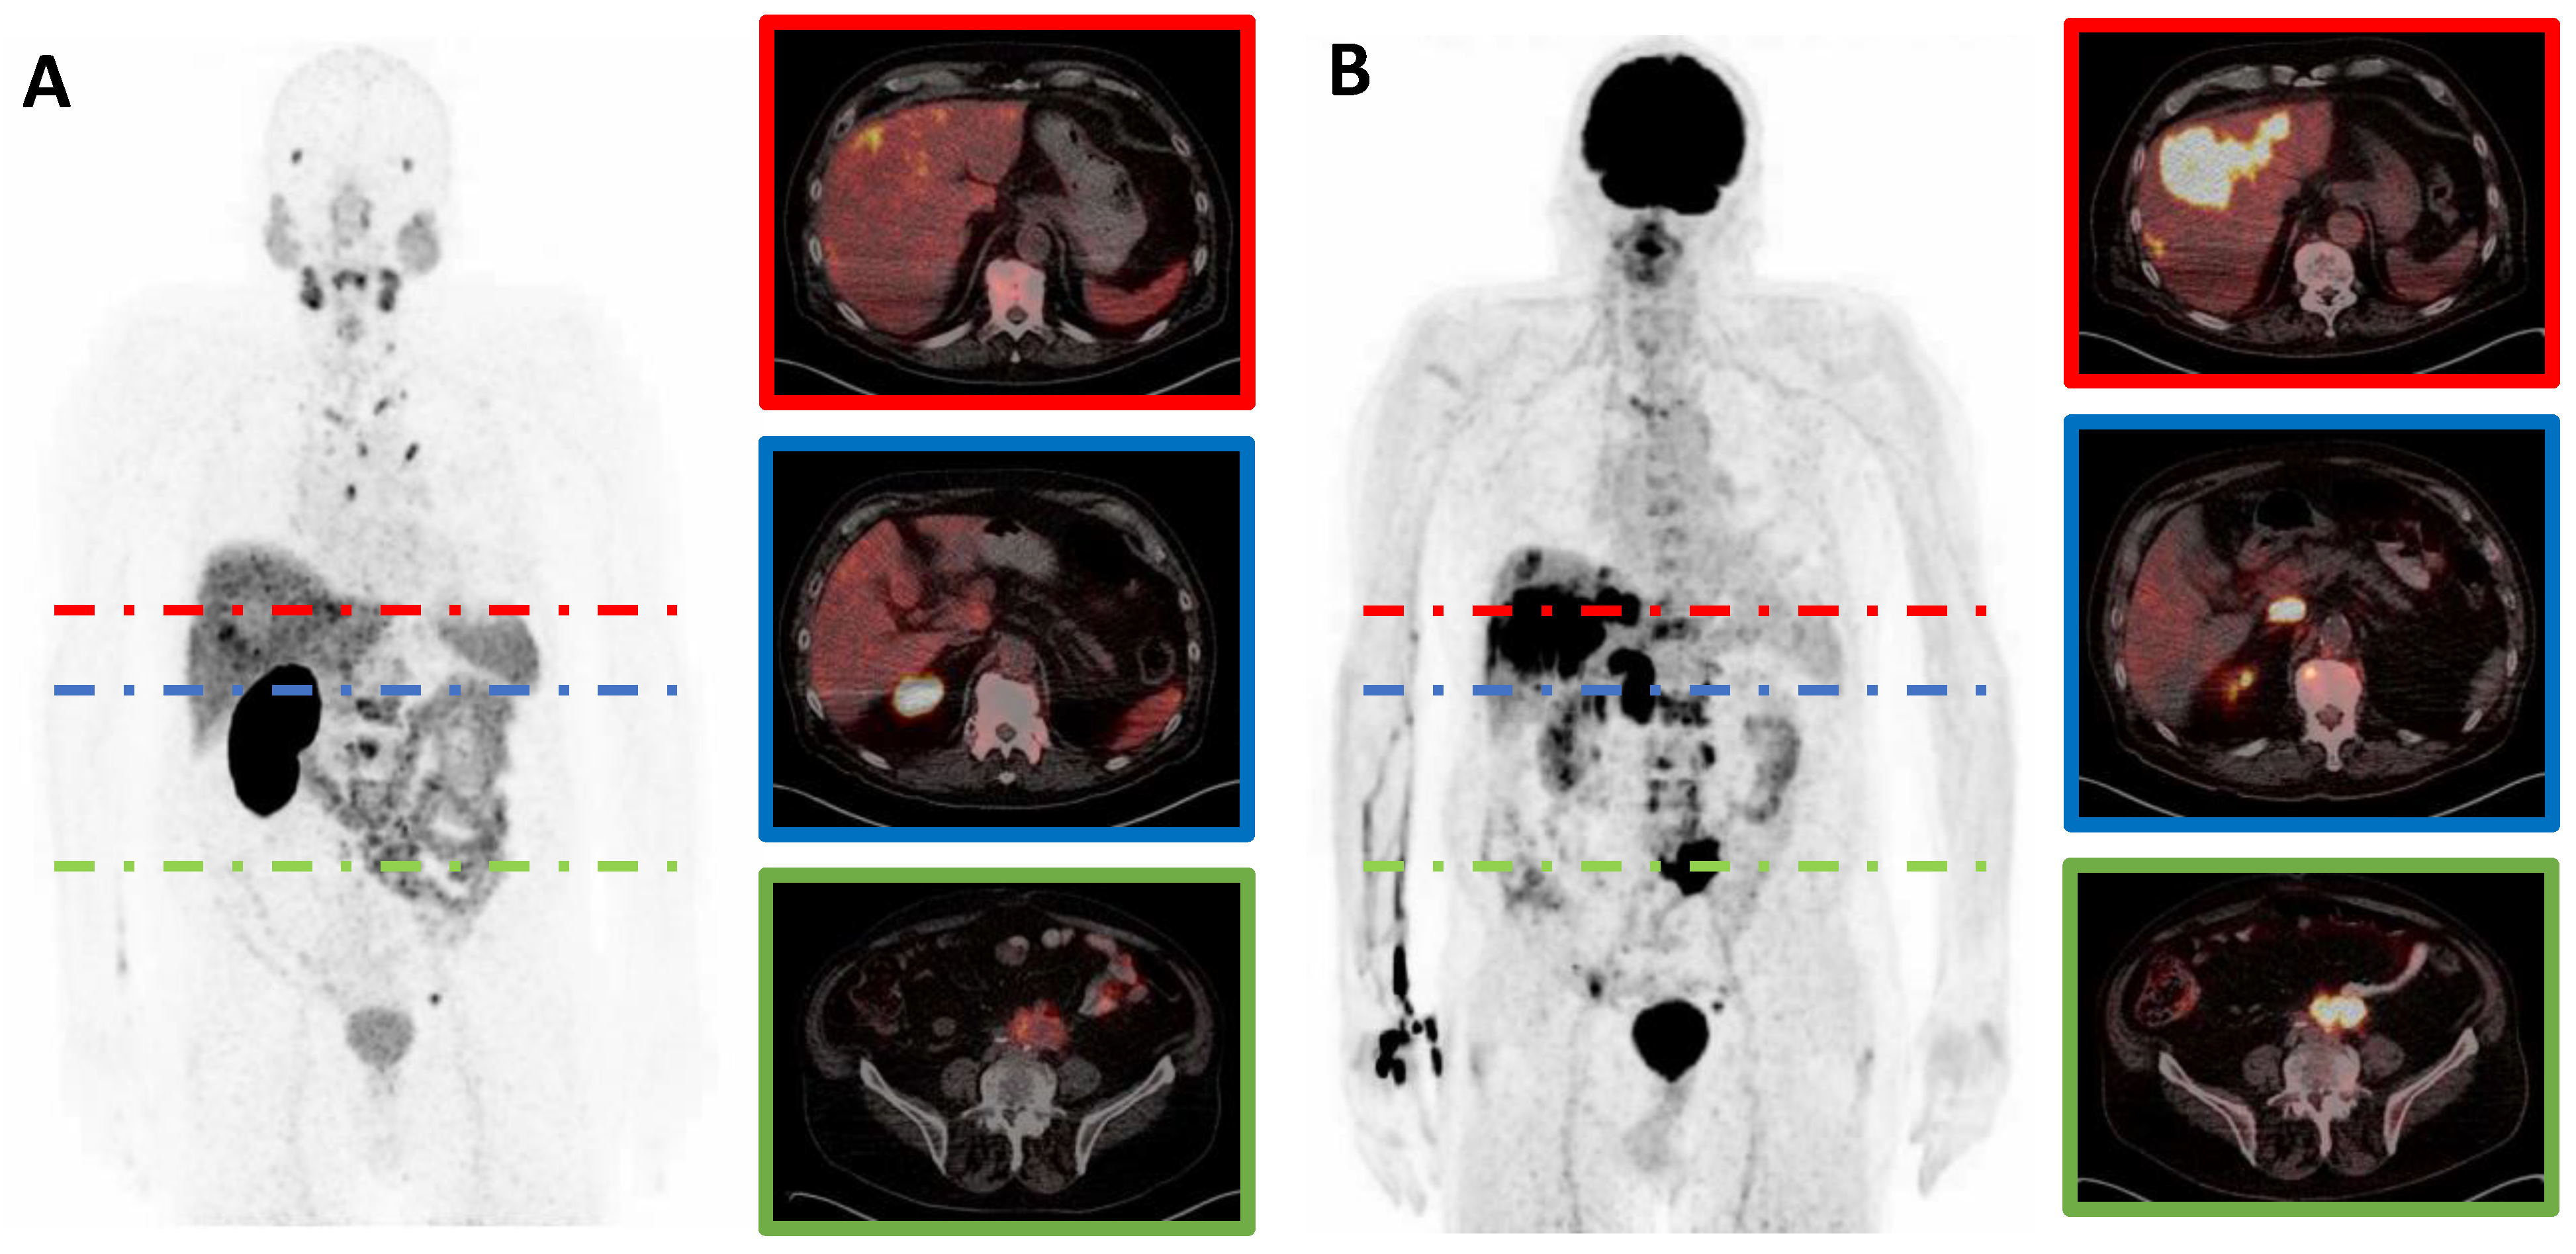

Out of n = 29 mCRPC patients included in this retrospective study, 17/29 (59%) patients showed at least one mismatch metastasis in combined [18F]FDG and [68Ga]Ga-PSMA-11 PET imaging (after a median of three cycles of PSMA-RLT), whereas 12/29 (41%) patients did not show any mismatch findings (after a median of five cycles of PSMA-RLT). In a subgroup of patients with mismatch, the median number of mismatch-metastases per patient was 8 (range 2–36). These mismatch metastases were found in bone (84 lesions in 11/17 patients); in lymph nodes (27 lesions in 9/17 patients), in the liver (69 lesions in 9/17 patients) and in the lung (6 lesions in 3/17 patients). Median MTVm was 74.4 mL (range: 3.3–354.6 mL) per patient. Median TLGm was 607.8 mL × SUV (range 13.0–4974.1 mL × SUV) per patient. Median SUVmax of the most intense mismatch lesion on [18F]FDG PET/CT was 16.8 (range: 7.0–95.2). Figure 1 shows a representative example of an mCRPC patient with multiple mismatch findings. No correlation was found between PSA and either SUVmax (r = −0.25, p = 0.926), MTVm (r = 0.098, p = 0.708), or TLGm (r = 0.235, p = 0.364).

Figure 1.

[68Ga]Ga-PSMA-11 (A) and [18F]FDG (B) PET/CT images of a representative mCRPC patient with hepatic (red) and lymphonodular (blue and green) mismatch lesions. Note: mCRPC, metastatic castration-resistant prostate cancer.